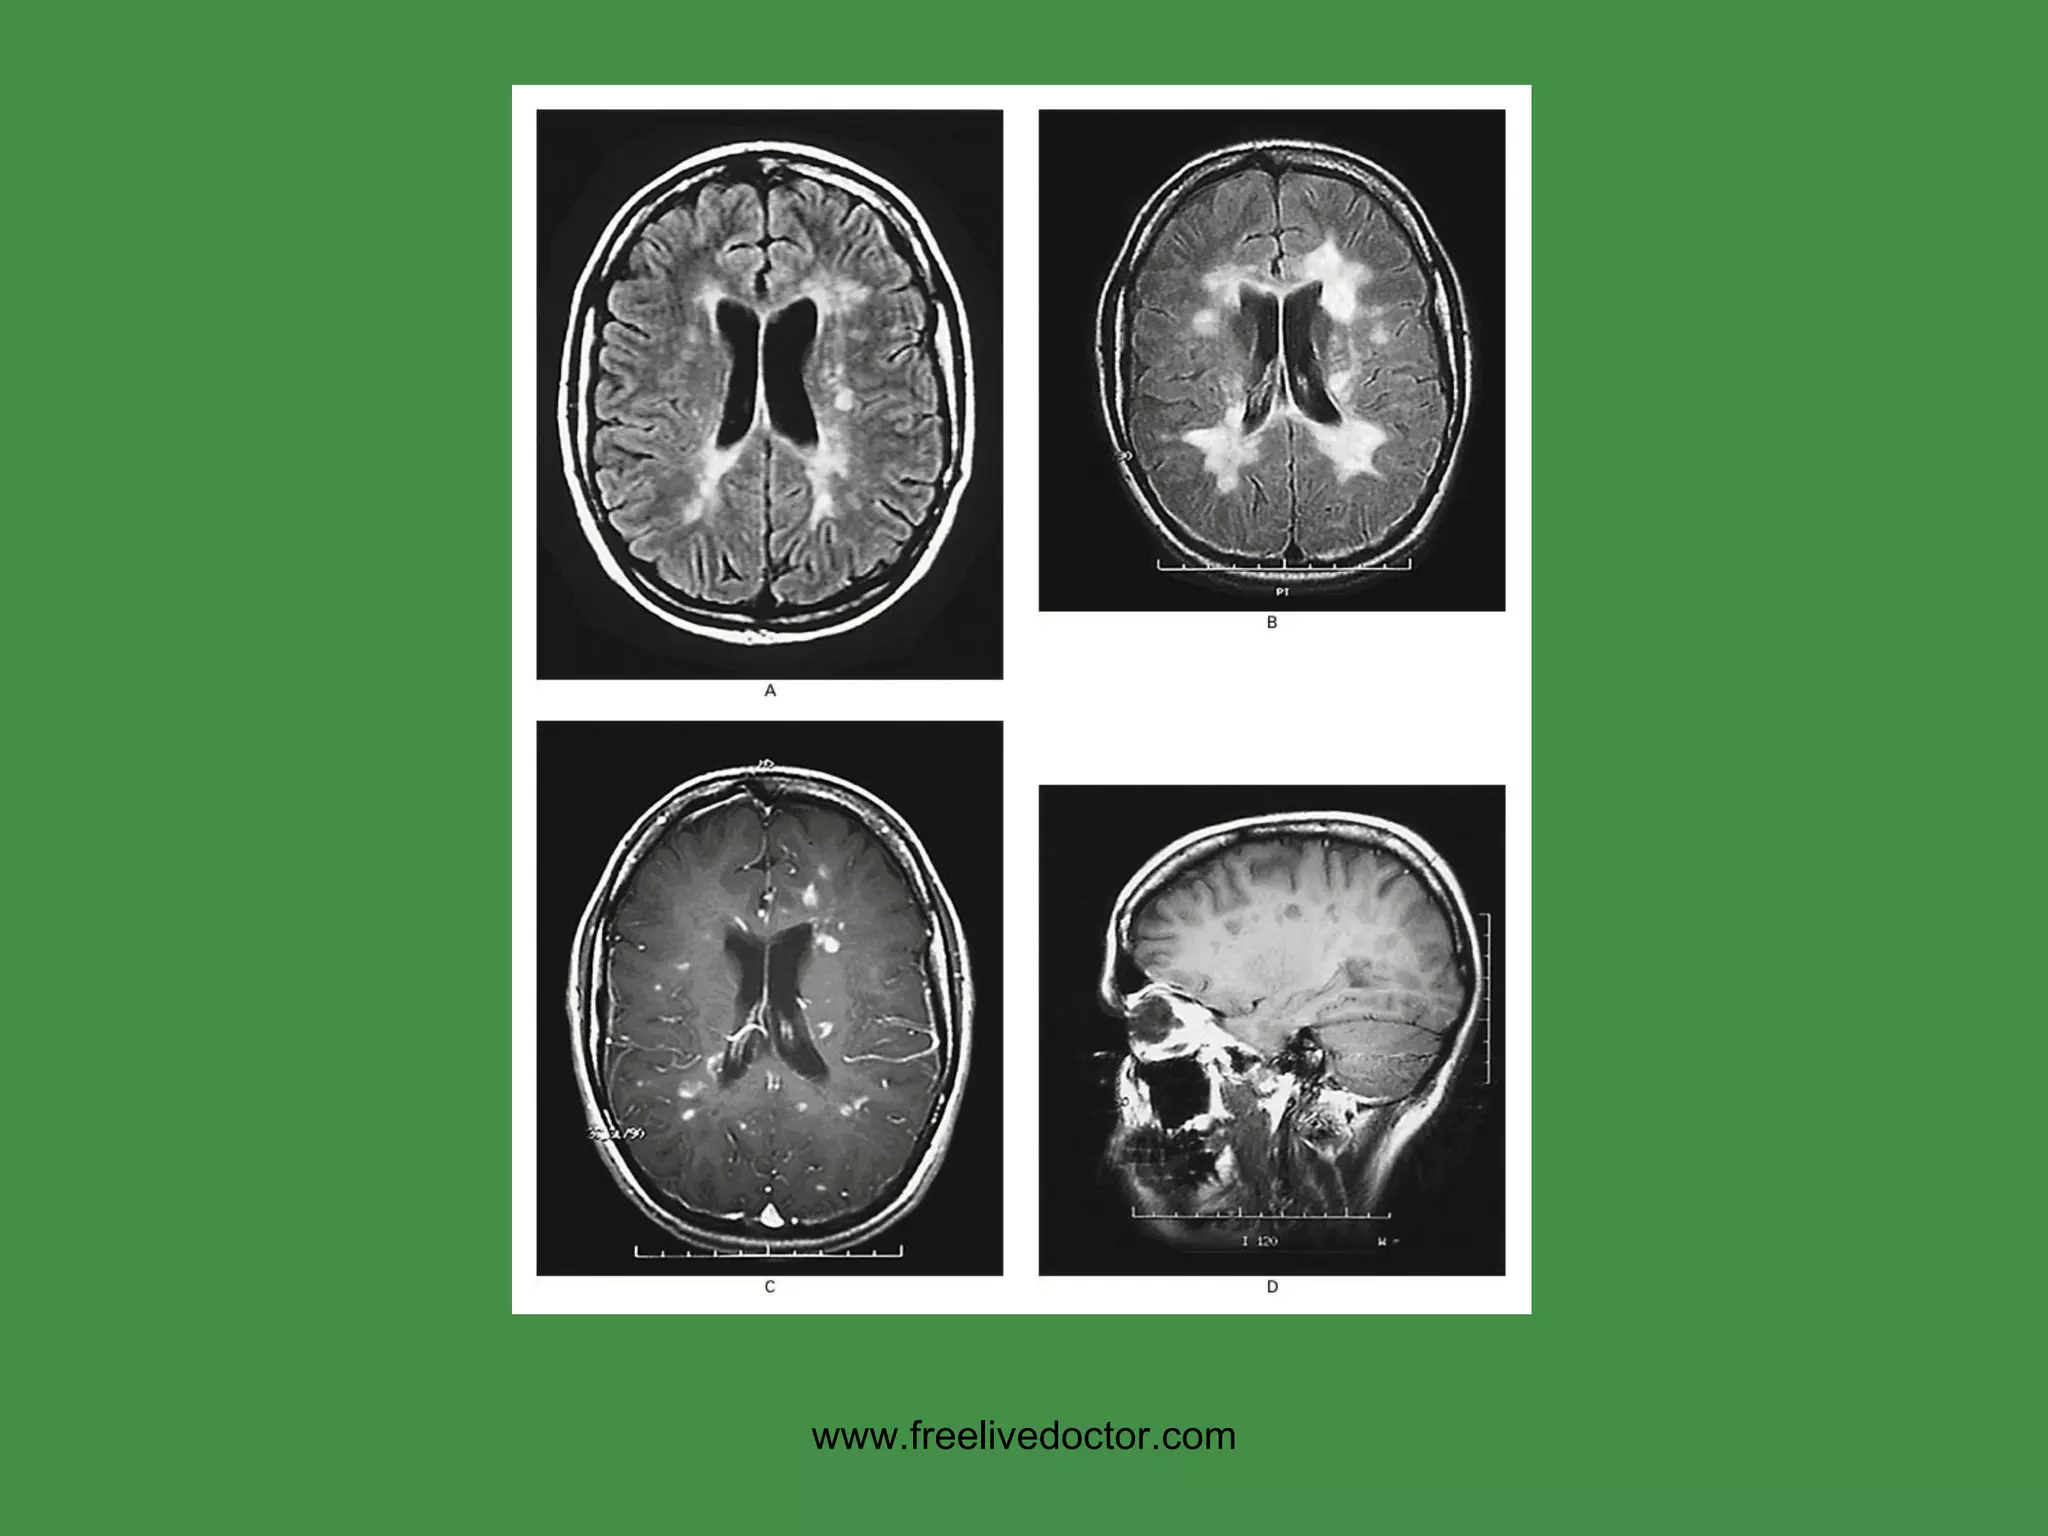

MS Cause:  ? USA prevalence:  1:1000  F>>M,  Ages: 30’s, 40’s Immune response primarily against CNS myelin (white matter) Regional area of white matter demyelination is called “PLAQUE” Increased CSF gamma globulin, i.e., oligoclonal bands Often presents with VISUAL problems EXACERBATIONS/REMISSIONS www.freelivedoctor.com

PLAQUES, MS www.freelivedoctor.com

VASCULAR DEMENTIA Associated with multiple infarcts, hence the name MID (Multiple Infarct Dementia) Lacunar infarcts Cortical microinfarcts Multiple embolic infarcts SECOND commonest form of dementia after Alzheimer www.freelivedoctor.com

• #91 Demyelination is associated with gliosis and edema, therefore bright signals on T2 weighted images

• #105 Demyelination, generically, is a NON-specific pattern of CNS reaction to injury of many types and usually goes hand in hand with edema and gliosis, If it wasn’t for the “edema” associated with demyelination, the “plaques” would not be seen on MRI.

• #106 The PLAQUE of MS is NOT like a plaque of skin diseases, i.e., it is not a raised lesion, but an area of demyelination.

• #107 MS gave MRI its first HUGE boom, by virtue of being able to detect these lesions, due to edema!

• #124 How would one differentiate MID from MS? Ans: MS is purely white matter. In this MRI we see grey matter lesions, so it is more likely MID rather than MS